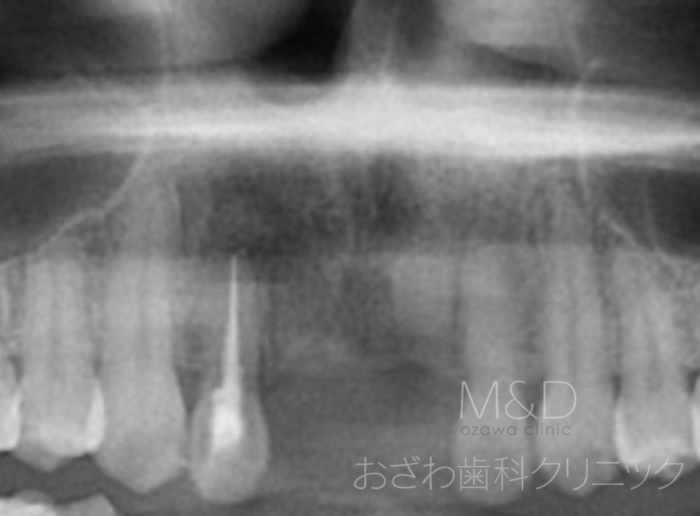

術前

主訴:前歯の欠損